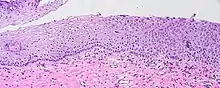

LEEP cone biopsy displaying normal cervical epithelium (far left) progressing to borderline koilocytosis, to LSIL, and to HSIL (far right).

A squamous intraepithelial lesion (SIL) is an abnormal growth of epithelial cells on the surface of the cervix, commonly called squamous cells. This condition can lead to cervical cancer, but can be diagnosed using a Pap smear or a colposcopy. It can be treated by using methods that remove the abnormal cells, allowing normal cells to grow in their place.[1] In the Bethesda system, the cytology can be graded as LSIL (low-grade squamous intraepithelial lesion) or HSIL (high-grade squamous intraepithelial lesion).